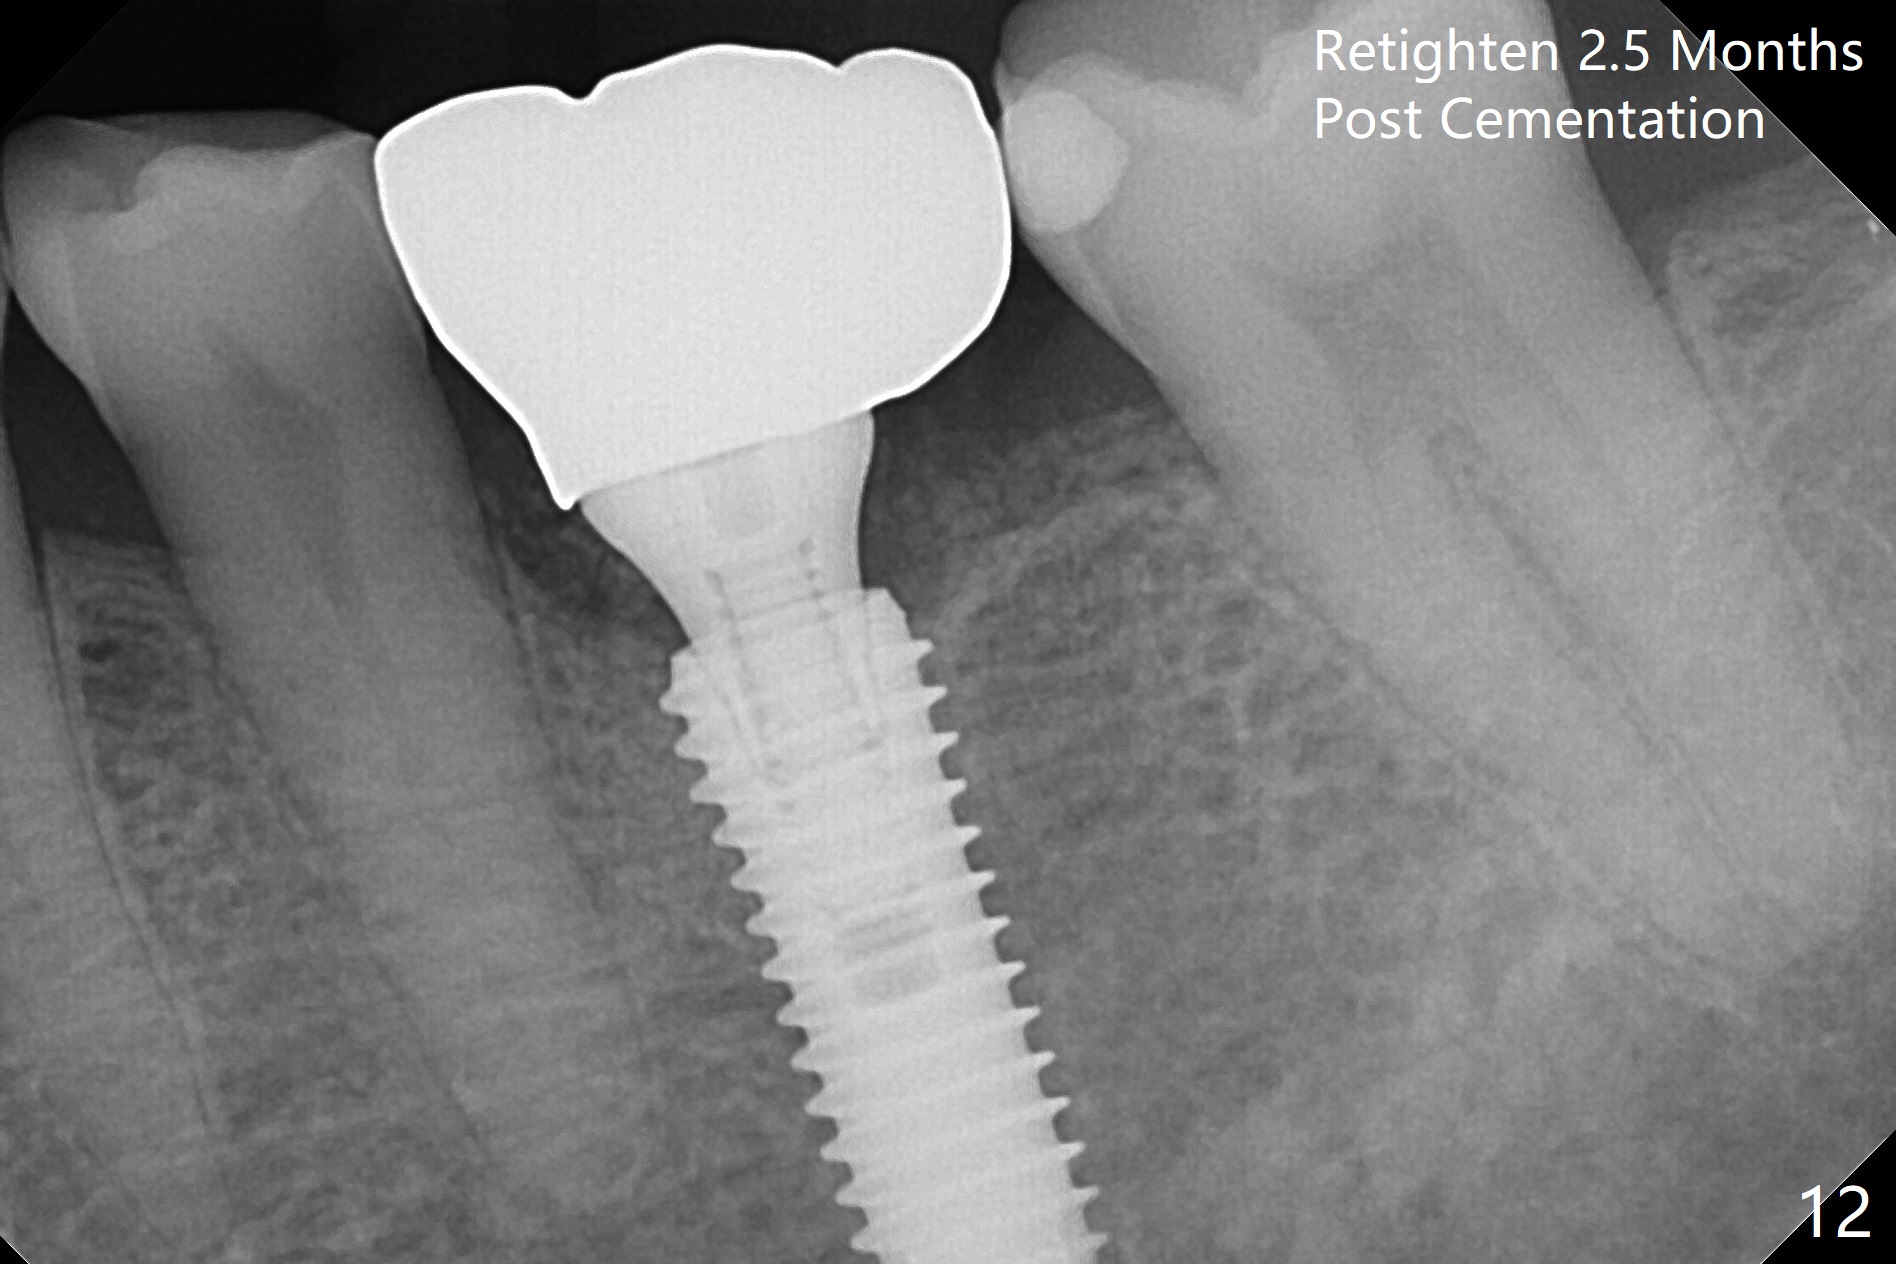

When the patient returns 9 months later, there is severe buccal gingival recession and abscess at #19 (Fig.1 *) with large mesial periradicular radiolucency (Fig.2 *). The septum is thin and the buccal crest is low after extraction (Fig.3 * (mesial root vertical fracture)). Osteotomy is initiated in the mesial socket immediately against the septum (Fig.4.5) with ~ 5 mm in the native bone. Due to severe buccal plate resorption, a shorter implant is placed (Fig.6; 5x15 mm in stead of 18 mm). There is at least 2 mm gap buccally for Vanilla Graft, which is also placed next to the implant and the neighboring root (Fig.7 *). There is clearance from the Inferior Alveolar Canal (Fig.8 red dashed line). Both the mesial and distal sockets heal 5.5 months postop (Fig.9), although the apical portion of the distal socket was not filled with allograft (Fig.7). The implant was placed mesial. The straight abutment (6.5x4(4) mm) (Fig.10) is changed to an angled one (5.5 x15 degrees 3 mm cuff (Fig.11)) before impression. The implant is also placed buccally. Therefore the implant position is far more important than its length. The abutment is retightened 2.5 months post cementation, which is related to mesiobuccal placement of the implant (Fig.12). An ideal trajectory is determined by drawing 2 horizontal lines (at crestal and apical levels: red lines in Fig.13), finding a central point of each line (vertical short line) and joining these 2 central points (Fig.14 pink line). In fact the ideal osteotomy should have been established distal to the septum in this case. Guided surgery may alleviate the issue. The crown is not loose, but the patient feels that the implant tooth cannot sustain mastication. In fact the screw is removed with hand driver (not wrench). The abutment hex is rounded and worn. A new 5.5x4(4) mm abutment is placed (without knowledge of previous use of an angled abutment) with mesial reduction to reduce undercut and buccodistal margin lowered to reduce gingival embrasure. It is that the straight abutment could decrease the chance of screw loosening. Otherwise the implant has to be removed for better trajectory.